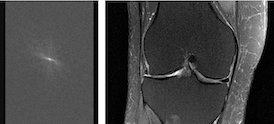

fastMRI